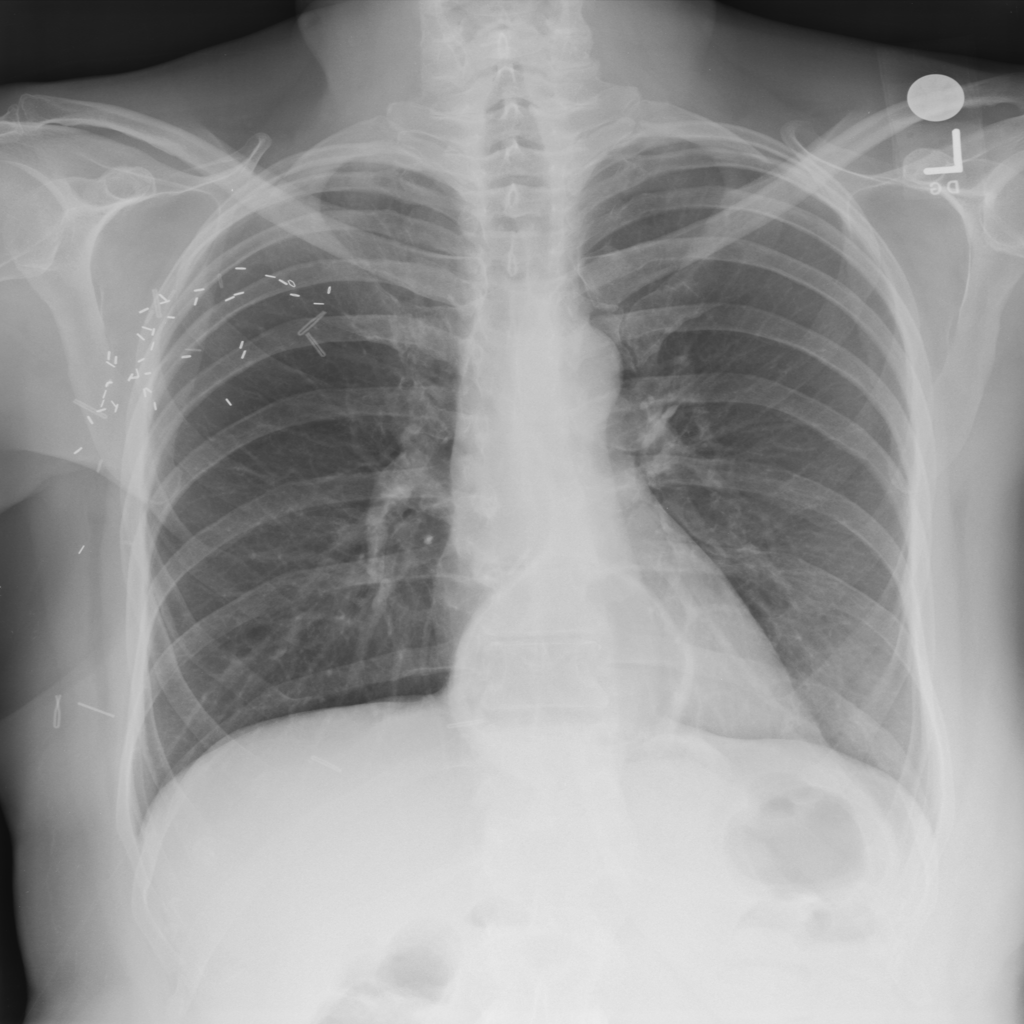

Showing up to 90 reference images for Hernia.

PAT-C048 · IMG-000Hernia

PAT-C048 · IMG-000

PA